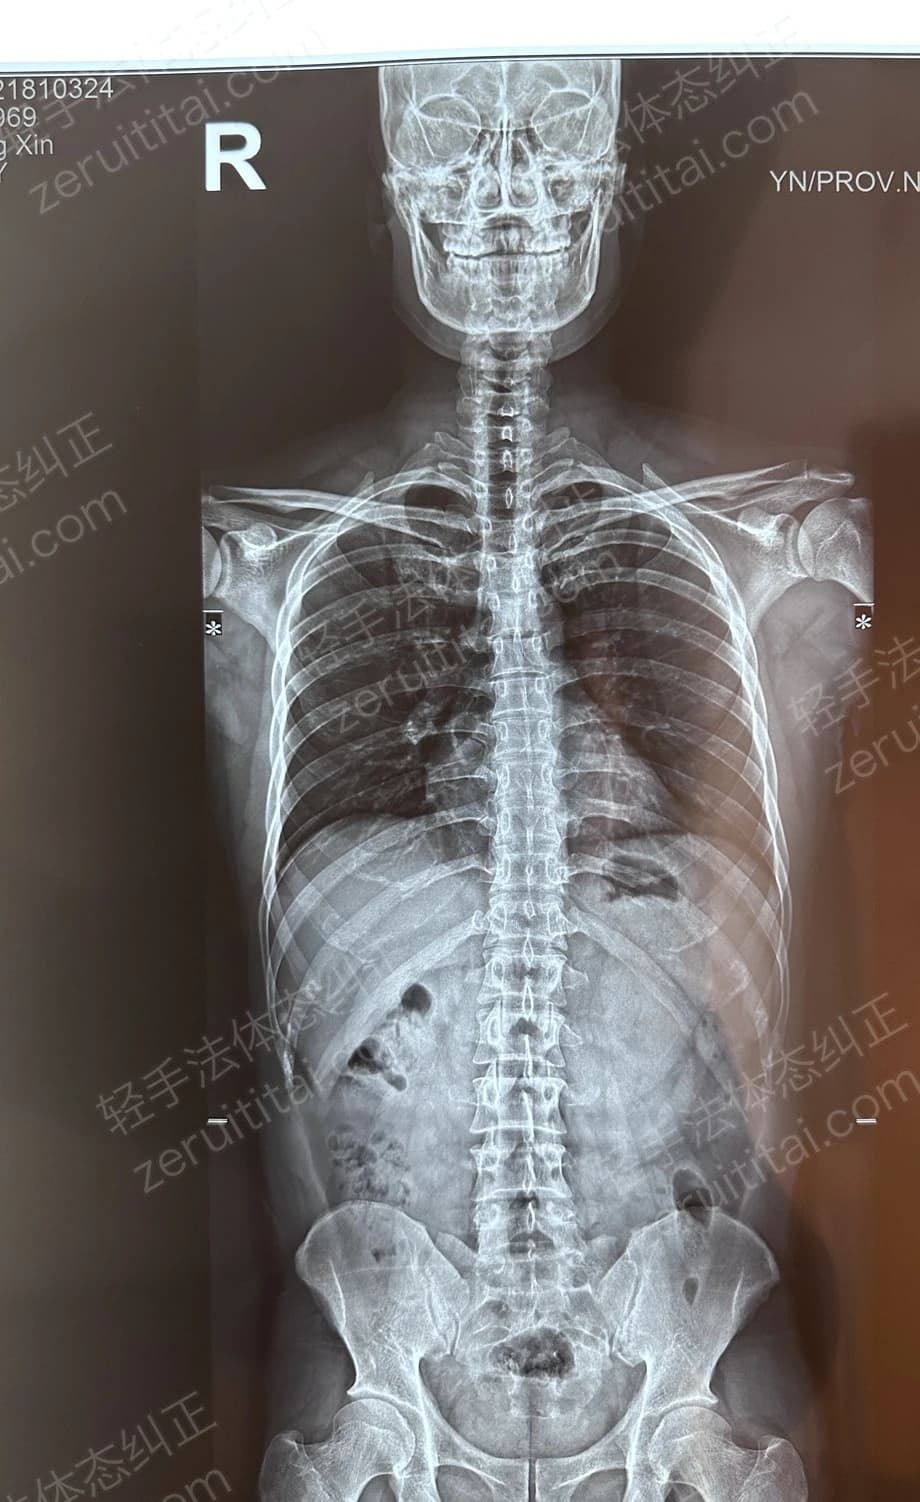

2022.09.27

第 2 次记录